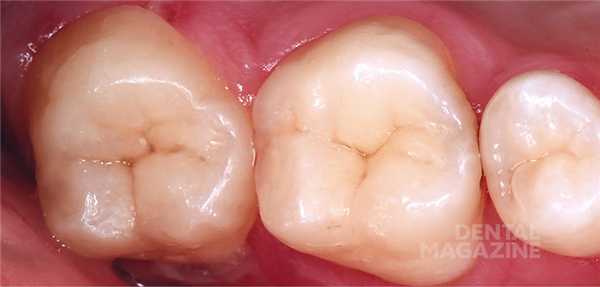

На рисунке 1 показана исходная ситуация.Классический фиссурный кариес зубов 16 и 17. Как и в большинстве подобных случаев, кариозный процесс протекает абсолютно бессимптомно.